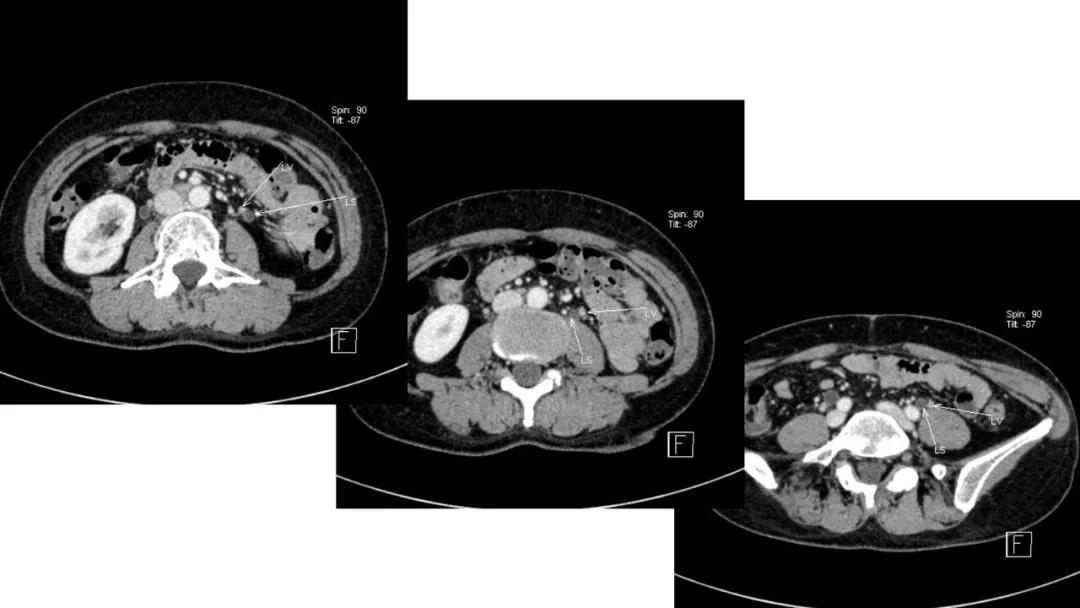

病例10

女,39 岁,体检发现盆腔肿块1月余

CA125:51U/ml

病理:左侧卵巢卵泡膜-纤维瘤